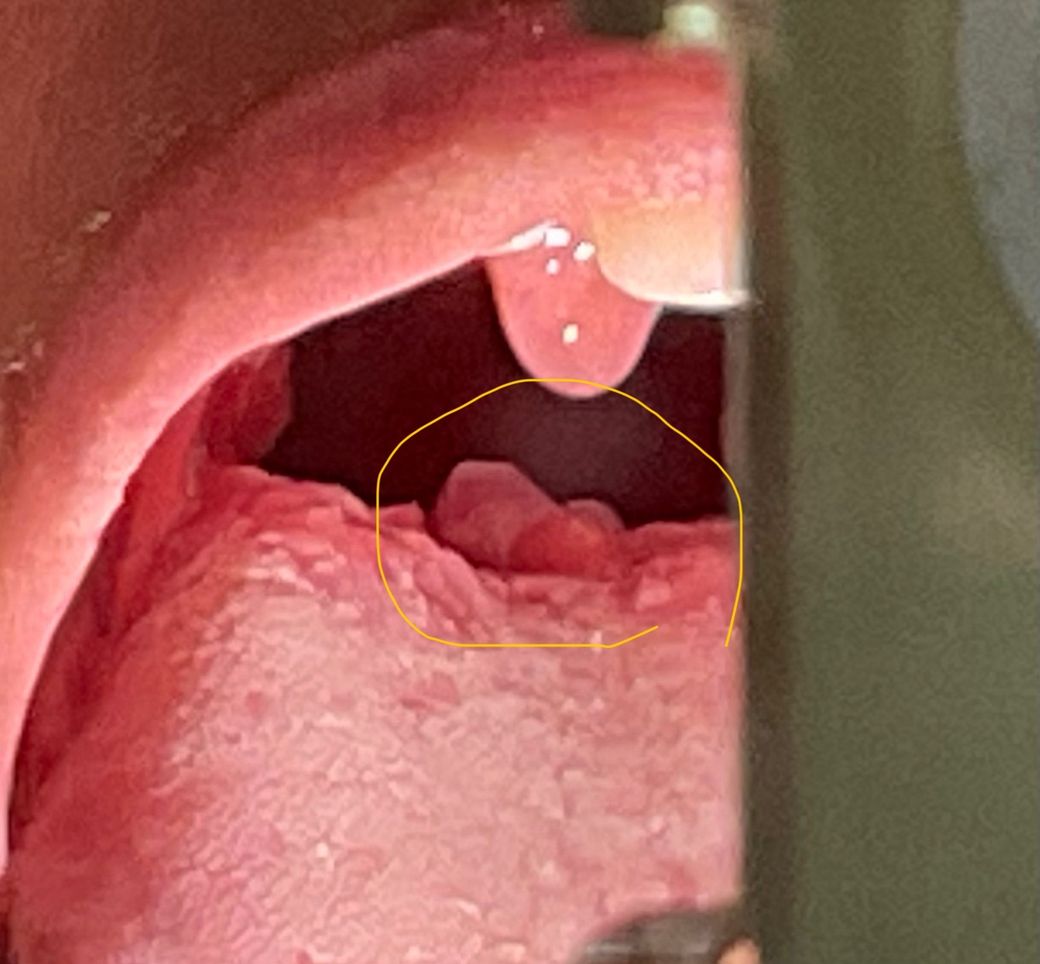

편도염이 생겨 이비인후과 가서 약처방 받았는데 설편도에도 생긴것 같은에 설편도얌 심한가요??? 음식먹으면 아파요. ㅠㅠㅠㅠ

사진상으로 보이는 구조물은 후두개 입니다. 설편도는 명확히 관찰되지는 않습니다. 편도염에 의해 상기 증상이 생긴것으로 보입니다.